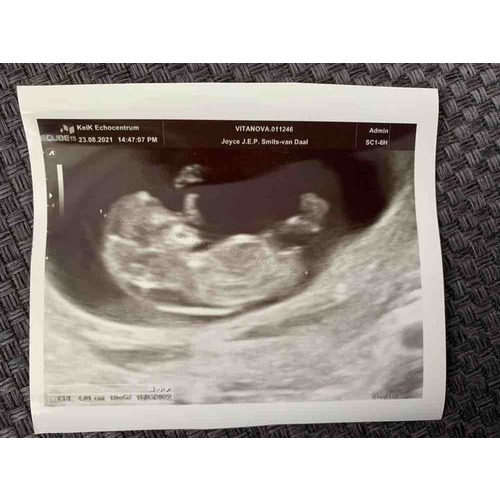

De nekplooi van ons kindje werd ook met 10+5 bekeken door de verloskundige (niet officieel gemeten) gelijk zagen wij een enorme bel met vocht aan de onderkant van de rug en ter plaatse van de nek. Na een eerdere miskraam met 8 weken schrok ik me rot. Verder bewoog het kindje en zag alles er goed uit.

Wij werden verwezen naar het ziekenhuis. Na daar 45 min te zijn onderzocht door de arts bleek dat er eigenlijk geen reden meer was tot onrust. Alles functioneerde prima naar behoren, deze man nam echt de tijd en legde alles zo goed uit, bewegingen, 2 hersenhelften, hart actie, ledematen, neusbotje, etc, en tot onze verbazing bleek dat de nekplooi (na meting) nog maar 2 mm was. De arts zei gezien de status voor de doorverwijzing is dit helemaal binnen de norm en zie ik nu geen reden voor direct vervolg onderzoek. Tranen van opluchting kwamen naar boven. De arts zei ook wij zien dit vaker als er voor de 11 weken naar gekeken wordt maar ik vermeld er wel bij dat het goed en terecht is dat jullie zijn doorverwezen.

Hier ook voor de 11 weken een verdikte nekplooi. Een week later in het ziekenhuis een GUO na de 11 weken en een nekplooi van 0,1 mm.